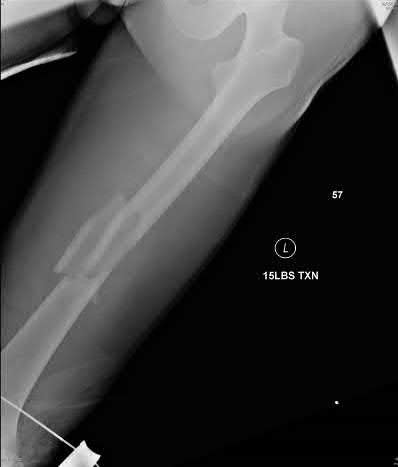

Question 30

A 30-year-old male is admitted after suffering a closed tibial shaft fracture. Twelve hours later, he complains of severe pain out of proportion to his injury and pain with passive toe extension. Which of the following pressure measurements is the most reliable threshold indicating the need for an emergent fasciotomy?

Explanation

The delta pressure (Δp) is calculated as the diastolic blood pressure minus the intracompartmental pressure. A Δp of less than 30 mmHg is considered highly specific for acute compartment syndrome and is a standard indication for emergent four-compartment fasciotomy of the leg. Absolute pressures are less reliable because tissue perfusion depends on the perfusion gradient.